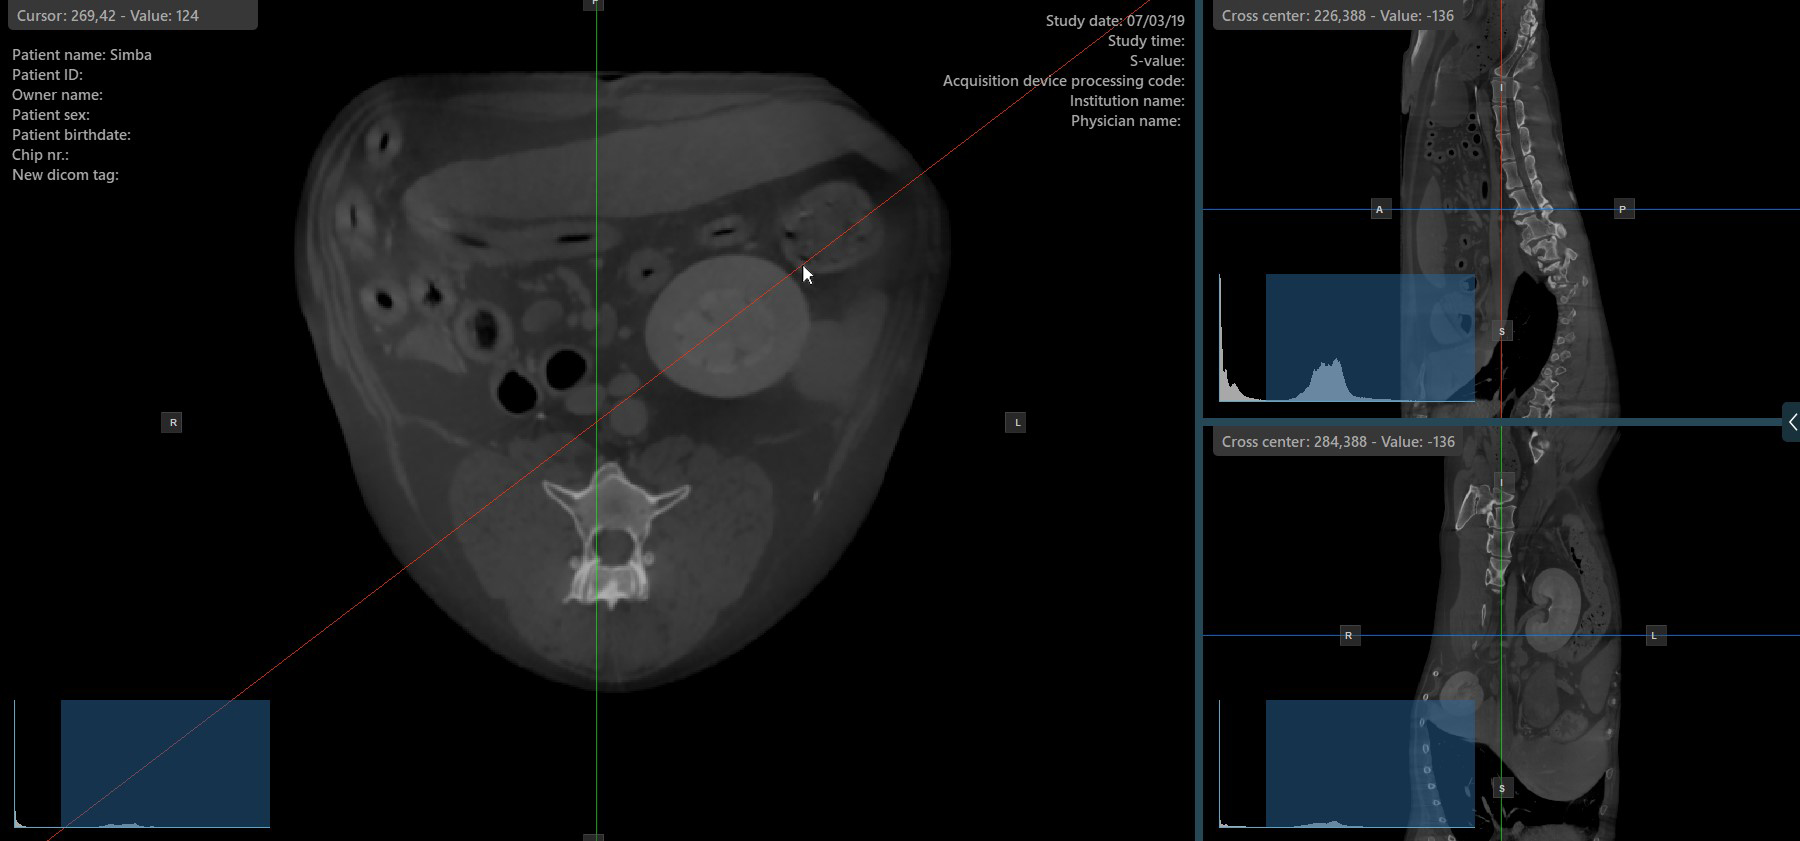

Das Ändern der Rotation eines Slicers verändert die Orientierung der entsprechenden Bildebenen. Einzelne Slicer können mit dem Werkzeug Select Item (Default)

ausgewählt werden, das standardmäßig der rechten Maustaste zugewiesen ist.

Sobald der bestimmte Slicer ausgewählt ist, ziehen Sie ihn in die gewünschte Richtung, um ihn zu drehen. Die Orientierung der entsprechenden Bildebene ändert sich entsprechend.

Standardmäßig kann jeder Slicer separat rotiert werden. Das entsprechende Symbol in der linken Werkzeugleiste des CT-Viewers wird deaktiviert, wenn die Slicer einzeln rotiert werden.